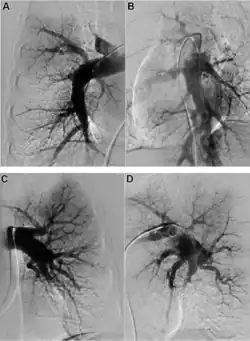

Early diagnosis remains a challenge in CTEPH, with a median time of 14 months between symptom onset and diagnosis in expert centres.[7] A suspicion of PH is often raised by echocardiography, but an invasive right heart catheterisation is required to confirm it.[6] Once PH is diagnosed, the presence of thromboembolic disease requires imaging. The recommended diagnostic algorithm stresses the importance of initial investigation using an echocardiogram and V/Q scan and confirmation with right heart catheter and pulmonary angiography (PA).[8]

Both V/Q scanning and modern multidetector CT angiography (CTPA) may be accurate methods for the detection of CTEPH, with excellent diagnostic efficacy in expert hands (sensitivity, specificity, and accuracy of 100%, 93.7%, and 96.5% for V/Q and 96.1%, 95.2%, and 95.6% for CTPA).[9] CTPA alone cannot exclude the disease, but may help identify pulmonary artery distension resulting in left main coronary artery compression, pulmonary parenchymal lesions (e.g. as complications from previous pulmonary infarctions), and bleeding from bronchial collateral arteries.[10]